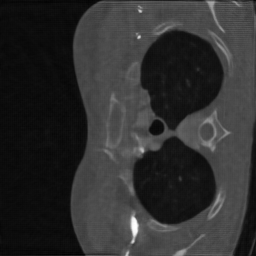

Computerized tomography

We consider parallel beam X-ray computerized tomography. It consists in probing line integrals of an object along a set of parallel lines that may be rotated and shifted. In this application the parameter represents the angles and shift at origin of the lines. The problem becomes blind if the object to image moves during the scan.

4.3.2 Computerized tomography

In this modality, we assume that the distribution of projection angles follows a uniform distribution centered on a vector of regularly spaced angles (see the red lines in first row of Fig. 1) and shift at origin . Hence, we have with and the random shifts are . These perturbations may reflect movements of the patient inside the scanner during the scan.

We trained the network using iterations using the ImageNet database. We initially used the Lung Image Database Consortium [7] database, but realized that it contains many improper slices (high noise, streaking artifacts, little contents…). We evaluated the algorithm on a curated version called LoPoDaP [58], containing less artifacts. The test dataset contains 4096 images.

As the blind inverse problem (5) requires differentiating the operator with respect to its parameters , we cannot use standard GPU-based libraries to compute the Radon transform [76]. We thus resorted to an homemade implementation that relies on a NUFT through the Fourier slice theorem. In order to reduce the important numerical cost and energy consumption of the experiments with CT reconstruction, we downsized the images to .

For CT reconstruction, we considered measurements coming from randomly perturbed versions of the equiangular pattern . The network is an unrolled ADMM ran for iterations. The perturbations belong to the family used for the family training. The perturbation is twice larger than what was observed during the training phase and does not belong to .

6.3.2 Computerized tomography

In this application, a model mismatch might occur due to the motion of a patient in the scanner. Correcting this mismatch is essential. Not accounting for it, can result in severe artifacts including some details loss and blur as can be seen in Fig. 6.

To identify the forward model, we ran the Adam optimizer on the parameters for iterations. In this application, represents the angle of the parallel shots and their shift at origin. All the reconstruction methods are able to significantly reduce the model mismatch, passing from maximal angles shifts of 7 degrees to less that 1 degree. Similarly, the shifts at origin are reduced from more than a pixel to about pixel. The reconstruction performance is significantly improved after estimating the forward model with PSNR increases of dB and more. The neural network trained on a family provides the best reconstruction results on this example.

Similarly to blind MRI, Table 4 shows that the “deep unrolled prior” method consistently provides good estimates of the forward model and significantly improves the reconstruction quality for the CT experiments.